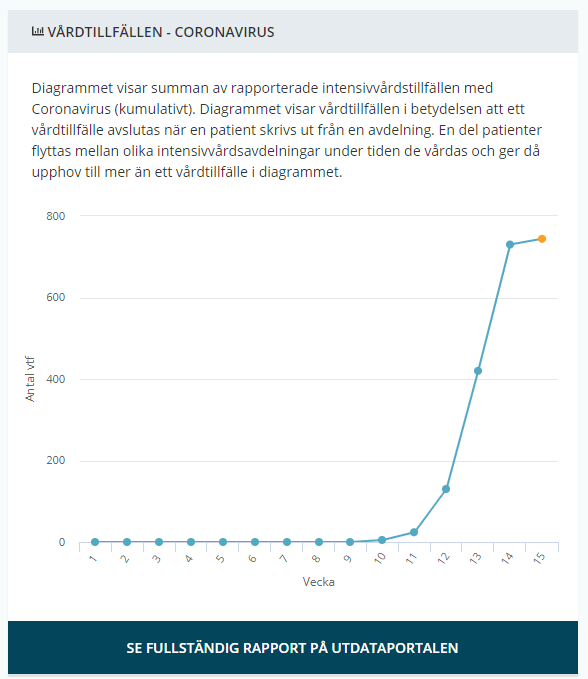

ICU [SWE]

New Covid-19 patients Being Treated at the ICU in Sweden.

(Number of COVID-19 cases over time in Sweden, updates during mornings at 14:00 so todays numbers are not yet complete until the next day).

- Intensive care Sweden: *

- 748 COVID-19 confirmed patients treated in the ICU in total so far

- 10,3 days from symptoms to ICU

- 24,6 % women

Total number of recorded of COVID-19 patients needing ICU care each week. From Week 10 it seems to more than triple each week for the first 4 weeks. From week ten: 5 → 24 → 129 → 424 → 746 → (939 this week up until now, however since it’s only friday this weeks numbers are yet incomplete)